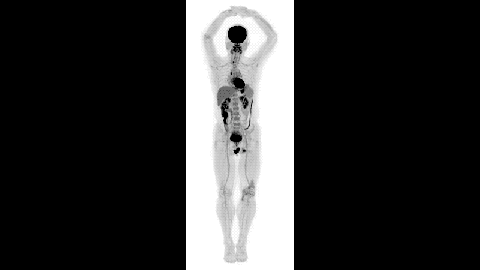

- New medical imager captures unprecedented 3D images of the human body.

- It’s 40 times faster than PET scans, and can use 40 times less radiation.

What do you get if you combine the technologies on which the two most successful medical imaging devices — positron emission tomography (PET) and x-ray computed tomography (CT) — are based? You get EXPLORER, the stunning new scanner that can capture an amazingly detailed 3D image of the entire human body in 20–30 seconds.

EXPLORER’s super-fast capture rate — it can scan a body region in about a second — also allows it to take movies of specially-tagged medications and radiotracers as they make their way through a body.

EXPLORER is 40 times as fast as a PET scanner, making it more feasible to do repeated studies on an individual, and, of course, there are the movies that can provide an unprecedented look at the in-body progress of radiotraceable agents. EXPLORER’S also 40 times more sensitive than PET scanners, so it will cause patients to be exposed to far less radiation during diagnosis than traditional PET or CT scans.